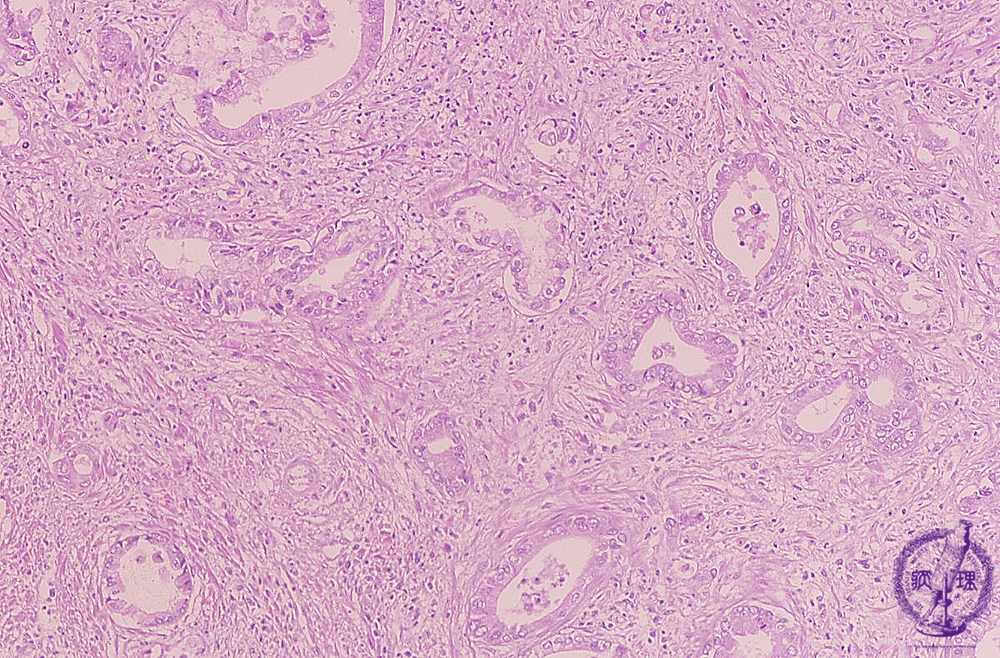

• š(13)Intrahepatic bile duct cancer (adenocarcinoma)

Microscopic image (HE stain, intermediate power): Moderately differentiated tubular adenocarcinoma consisting of columnar to cuboidal epithelium with abundant fibrous stroma.